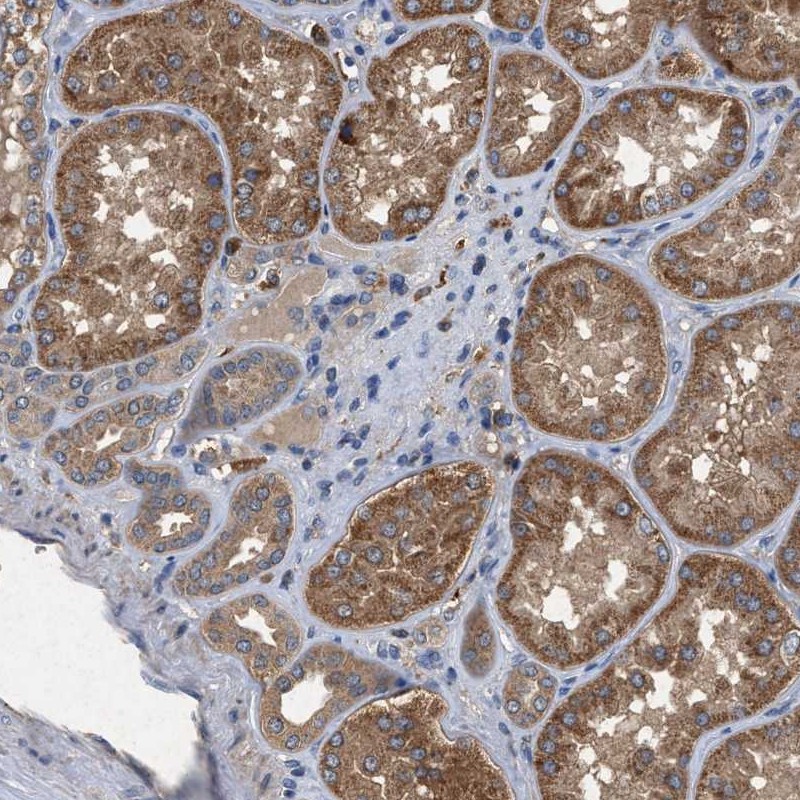

Immunohistochemical staining of human kidney shows cytoplasmic positivity in renal tubules.